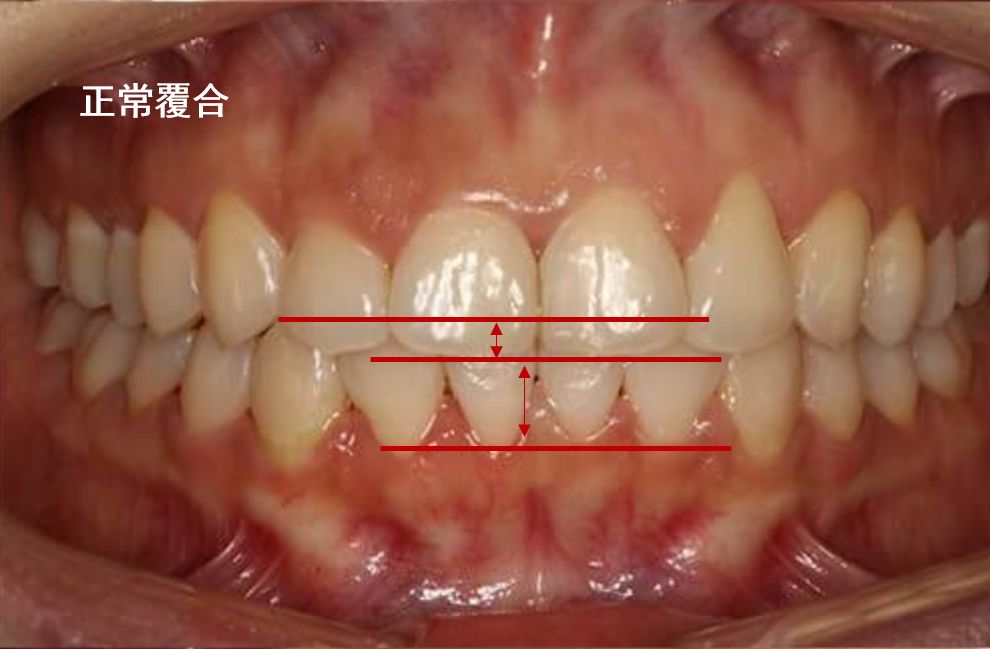

深覆合

深覆合是一种上下颌牙弓和(或)上下颌骨垂直向发育异常所致的错颌畸形。如果上牙包住下牙的范围超过了 2~3 毫米就是深覆合。是指垂直距离过大,是上下关系。

像这样